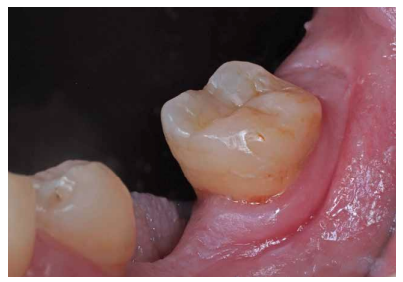

Se realizaron revisiones a 1 mes, 6 y 18 meses (Figuras 9 y 10), observando en la última radiografía de control mejoría en la lesión apical de la raíz distal. En todas las revisiones, la paciente se encontraba asintomática, la prueba de sensibilidad al frío fue fisiológica, al igual que la prueba de palpación, percusión y de mordida. El sondaje y la movilidad continuaban fisiológicos.

En el caso clínico expuesto, no se pudo realizar la revisión de los 12 meses debido a la situación de emergencia sociosanitaria causada por la COVID-19. A los 18 meses la paciente está asintomática, no presenta molestias a la palpación o percusión ni tumefacción y responde adecuadamente a la prueba de sensibilidad al frío. Radiográficamente no presenta signos de reabsorción interna ni patología periapical. Se considera que el tratamiento ha sido un éxito a nivel clínico y radiográfico2 .